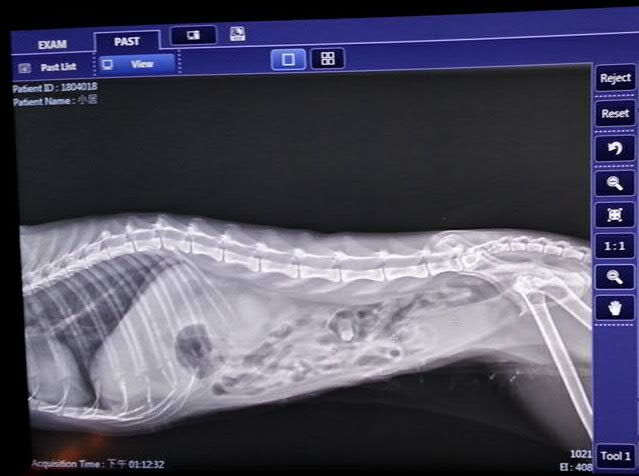

主題: 腎臟積水的三腳小居 申請者姓名: 臺北市支持流浪貓絕育計劃協會 花色: 申請日期: 2018-05-09 12:27:43 申請者部落格: 申請者臉書網址: http://admin.tnrtw.org/hospice_add.php 所在縣市/合作醫院: 台北市/澄諾動物醫院 治療費用: 19629元 需求人數: 43人 已結案 (2024-06-01 13:12:27) 報名人員: 柔(已付款)、Jube(已付款)、Jube(已付款)、EPT(已付款)、Lannie Lin x3(已付款)、YLC(已付款)、littlecut(已付款)、Naommi x2(已付款)、胖肯尼(已付款)、小伶 x6(已付款)、Janney x2(已付款)、Isabel Liu x10(已付款)、壞壞(已付款)、Moon x2(已付款)、Sugar Hung(已付款)、monilovecat(已付款)、Isabel Liu(已付款)、Isabel Liu x4(已付款)、Sol x2(已付款)、Tzu Ning Kuo(已付款)、 候補人員: 動物病情說明: 4/16 小居看診 澄諾

體重:2.1kg

體溫:36.8

看診情形

口腔檢查看到右邊牙齦有處類似組織爛肉,已發出不好味道,體重很輕, 體溫過低。

醫生為她抽血檢驗,稍晚會告知檢驗結果,可能視情況為她上點滴、鎮靜做進一步檢查及醫療,所以先將小居留院,照X光、血檢、尿檢、超音波等檢查,醫師診斷小居口腔的潰爛可能是腎臟問題引起的,有水腎現象。動物近況說明: 後轉泌尿科專科醫師治療 持續住院中